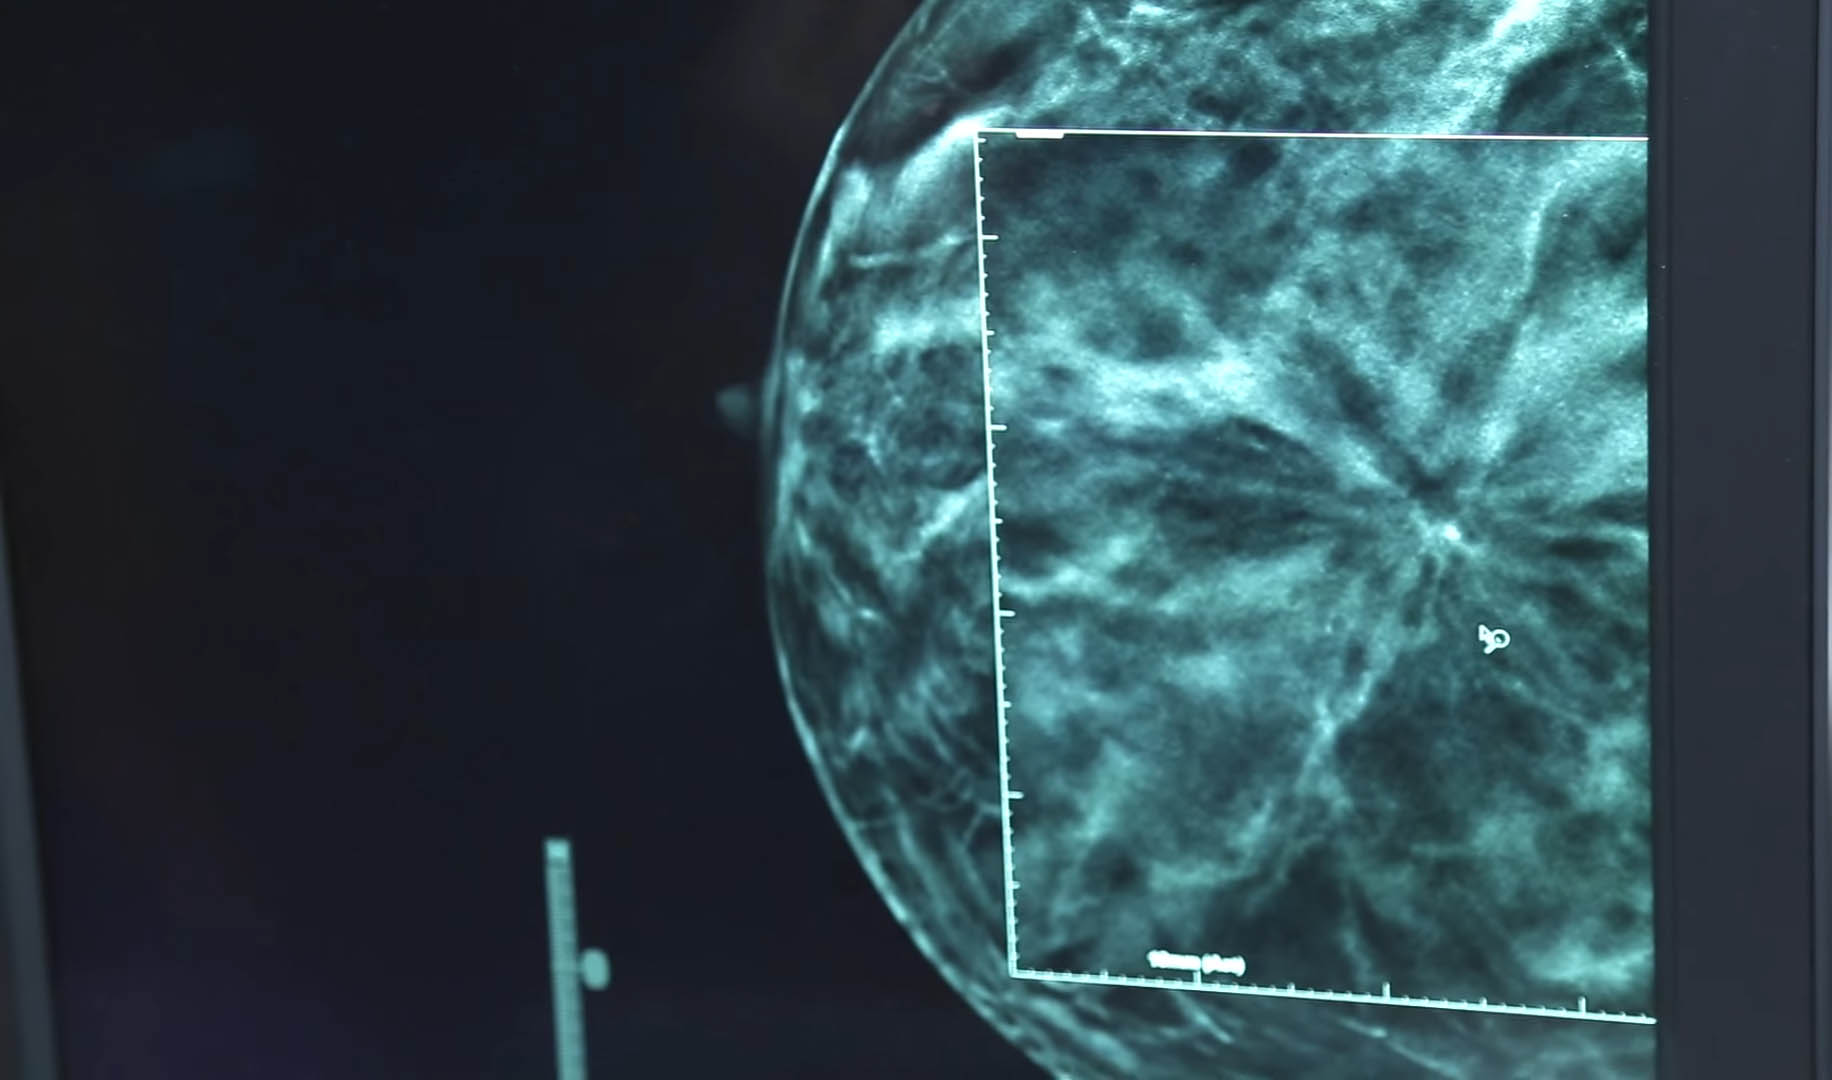

Andover Medical Center’s Women’s Imaging Service has adopted new digital breast imaging technology that results in better detection and fewer false alarms. It’s called 3D Tomosynthesis, and we are the first in the area to offer it. 3D Tomosynthesis is available at both Andover Medical Center and the South Pavilion at Lawrence General Hospital.

Traditional two-dimensional mammography equipment is stationary as the x-ray source takes a picture through the breast. Digital breast tomosynthesis uses a moving x-ray arm that passes in an arc over the patient’s body. The technology gives doctors more confidence in reviewing images, particularly in younger women with more dense breast tissue, or in women with a lot of breast cysts or calcifications. Viewing the breast in three dimensions gives doctors more information to determine if a lesion is something benign like a cyst, or something that needs further treatment.